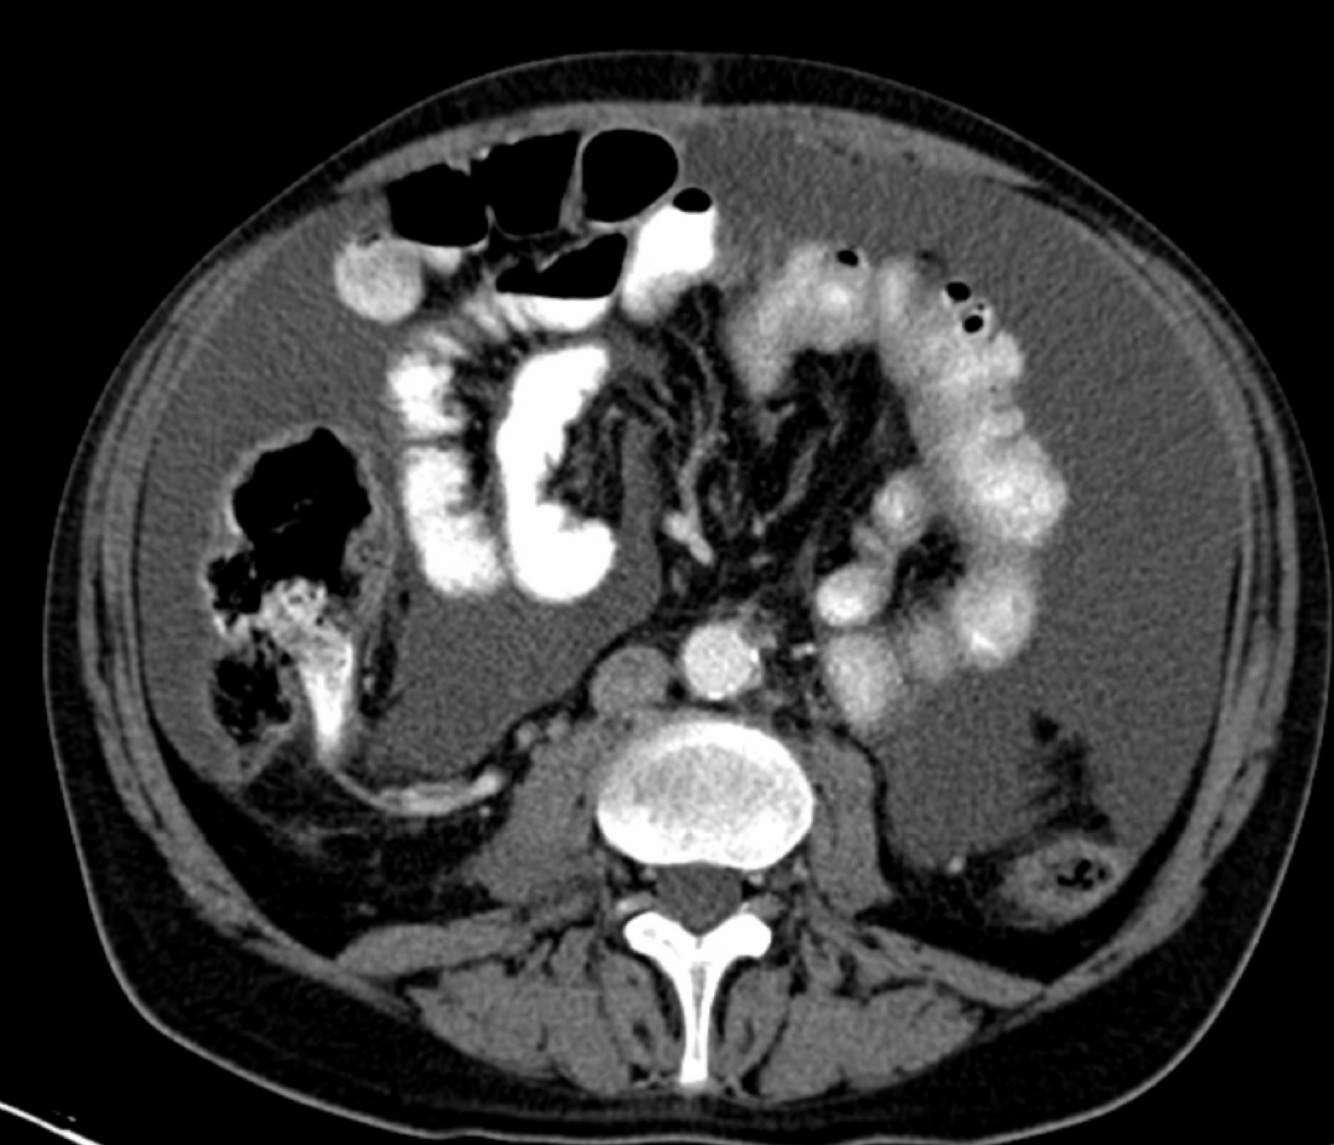

5

Q

A

1. Descending colon

2. Mesentery

How well did you know this?

1

Not at all

2

3

4

Perfectly